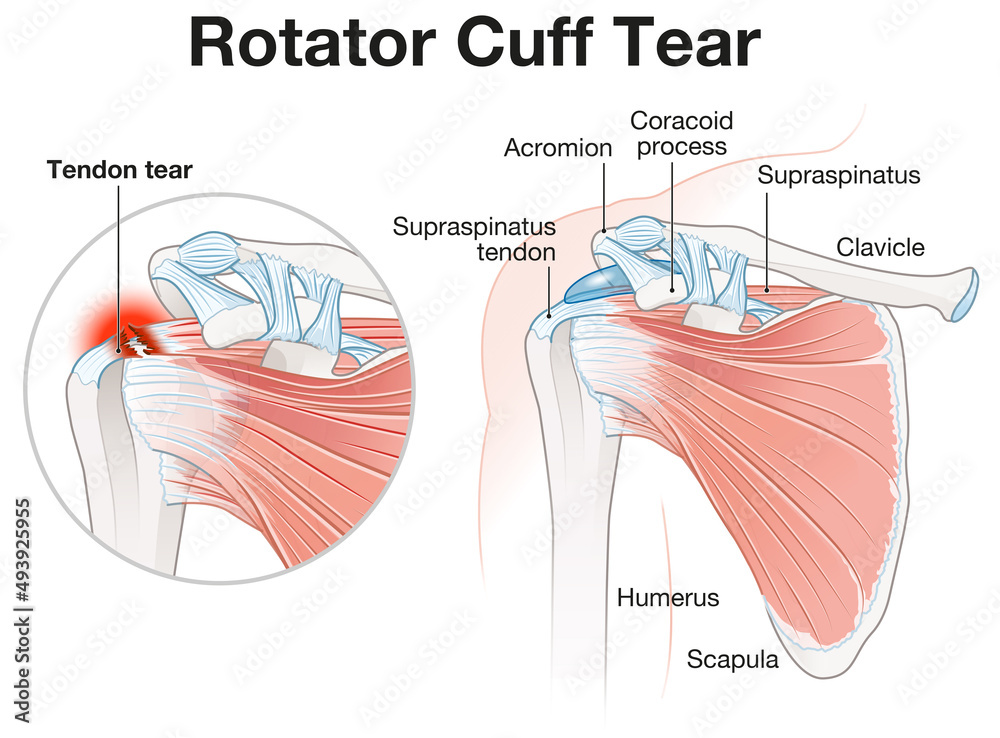

Фотографии мышц ротаторной манжеты плеча